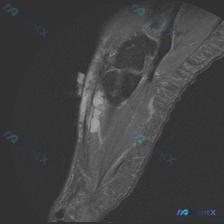

看到这个有意思的病例,整理了完整的分析思路分享给大家。 病例核心影像信息 这是一张踝关节MRI矢状位T1加权图像,原始疑问是观察到「软组织液体」,系统影像评估结果如下: 1. 骨性结构:各骨皮质连续,无骨折、骨质破坏,骨髓信号均匀,关节对位正常,关节面光滑,无明显骨赘或软骨下囊肿 2. 韧带肌腱:跟...